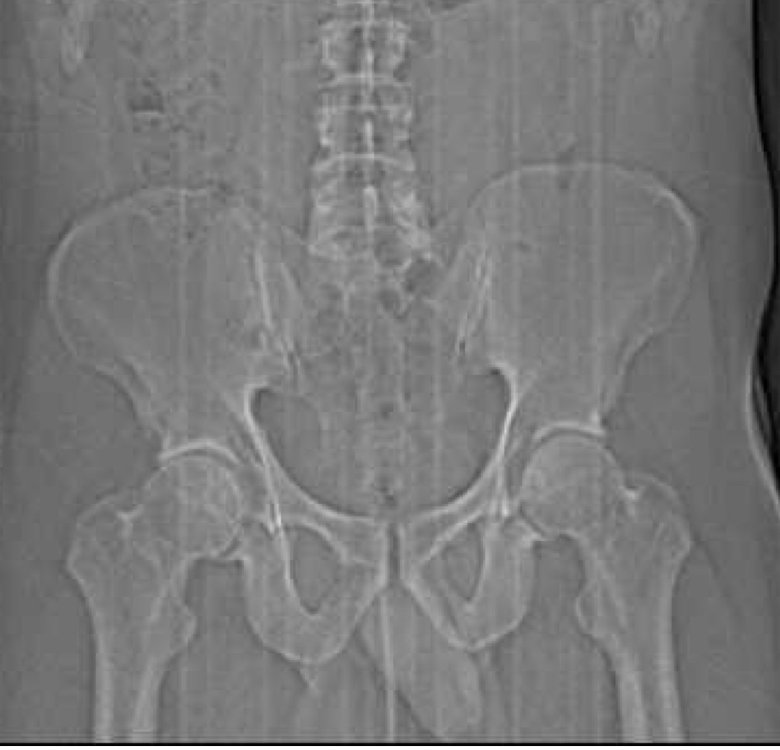

avgjoe913 Posted June 17, 2025 Report Posted June 17, 2025 (edited) Fun fact: dicks are visible on X-Rays! I recently had an X-Ray done of my hip, and after the appointment was over, I remembered that I'd previously seen something about dicks showing up on X-Rays (it was a thing that happened with the tennis player Andy Murray, you can look it up). The doctor did go over the X-Ray with me during the appointment, but we were obviously focused on my hip (which is fine), so I was very curious to see if I'd notice anything when looking at it on my own in the Patient Portal. I thought maybe only bigger ones are visible, and at first that seemed to be the case - I couldn't see anything. But it's sort of like those Magic Eye pictures - once you look at it for a little while and your eyes and brain figure out what they should be looking for, you see it. And it's certainly there - a shadowy but surprisingly accurate image of my penis, the top part of my scrotum, and my thigh next to them. Like many of you guys, it's basically just a head when I'm totally soft, and that was obviously the case in this situation, so it sort of just looks like part of my pubic bone at first glance. Alas. If you look up other examples, bigger ones are much easier to see. It's kind of funny to look at. I'm surprised this is not more well-known, to be honest. Anyway, I'm not sure if I can post it here, so for now, PM me if you're interested in seeing it. If I get the OK from the mods, I'll post it. Edited June 17, 2025 by avgjoe913 Grimson, LilGonzalote, Grizz10231 and 2 others 5

avgjoe913 Posted June 21, 2025 Author Report Posted June 21, 2025 Ha, well then I guess I'll go ahead and post mine! It looks like the contrast or something is different on yours, not sure why that is. Seems like there's less detail, but can still easily see what you're packing, lol. Grizz10231, A-RB, grandstand and 3 others 5 1